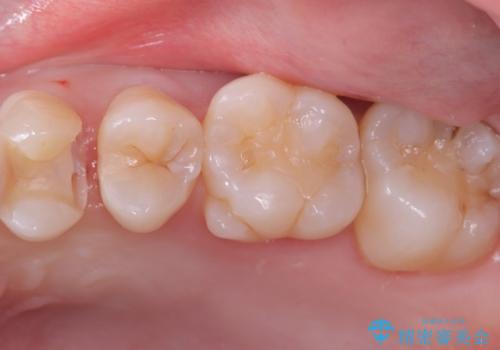

- 主訴:左上真ん中らへんの歯が欠けてしみるので治したい

審美性、適合性の良いセラミックインレーでのやり替えとなりました。

左上4近心に実質欠損を認め、遠心から咬合面にかけてはCR修復が施されていたため、MODインレー窩洞としました。

インレー接着操作時はラバーダム防湿を行っています。